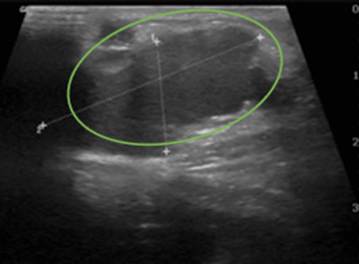

Infante de ocho años, llevado al servicio de urgencias por masa abdominal dolorosa de un año de evolución, localizada en el flanco izquierdo. Al examen físico se encontró una masa violácea, firme y dolorosa en el flanco izquierdo, sobre la cresta ilíaca, de aproximadamente 8x4 cm. La ecografía abdominal informó una lesión quística multiseptada versus estructuras cilíndricas vasculares dilatadas de 13x3,2x2,1 cm, sin flujo Doppler en su interior, sin componente sólido (Figura 2). En la resonancia nuclear magnética (RNM) se encontró una masa que deformaba la pared del flanco izquierdo y la pelvis izquierda, con septos intermedios, probablemente relacionado con hematomas (Figura 3). Se consideró malformación de bajo flujo, posiblemente linfática, y se le realizó manejo percutáneo con agentes esclerosantes (bleomicina 15 UI) (Figura 4), siendo dado de alta, con reingreso al mes por dolor abdominal y vómito. Una nueva ecografía abdominal informó hallazgos similares a los iniciales, además de cambios inflamatorios adyacentes. Se realizó manejo únicamente con antiinflamatorio no esteroideo con resolución de los síntomas. Posteriormente no se logró realizar seguimiento del paciente.